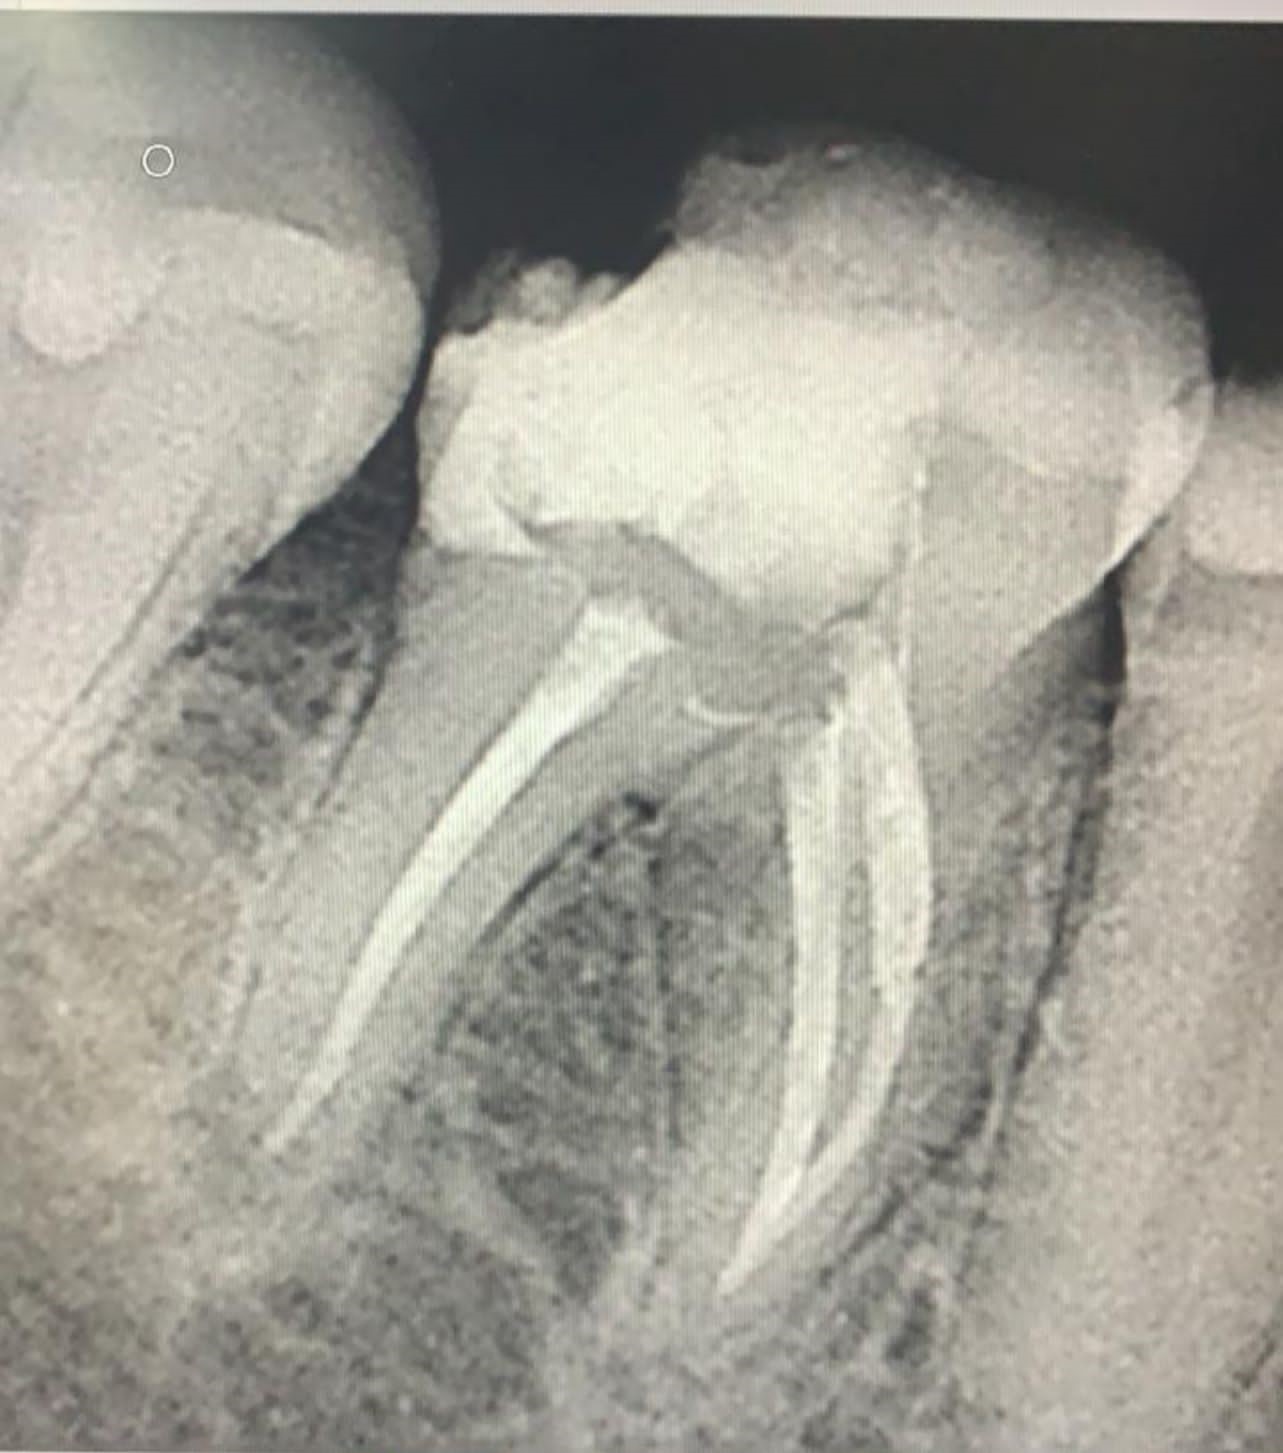

Galeria de Imagenes

Avances en procedicmiento de Endodoncia